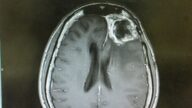

新發明用超聲波向腦癌細胞遞送藥物

膠母細胞瘤(glioblastoma)是一種最嚴重的腦癌,目前基本沒有治療辦法。美國一組研究者發明瞭...

2309天前